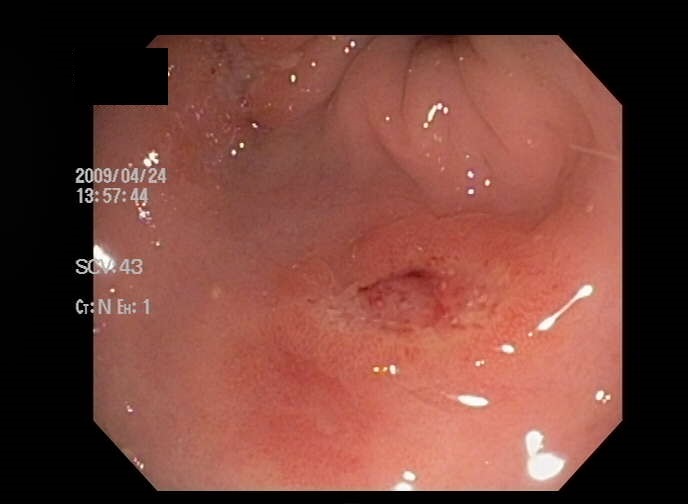

Images of 大牟田爆発赤痢事件

731からフクシマまで!!ウィーン訪問した長崎の被爆者が評価も…核兵器禁止条約締約国会議の成果は?「ウィーン宣言」「行動計画」「こんな判決出るとは」無念の原告 疲労と失望朝鮮人BC級戦犯裁判朝鮮人BC級戦犯裁判2.26事件東芝を沈めた原発事業「大誤算」の責任核被災に苦しむウイグルの人々731部隊フクシマまで2731からフクシマまで(5)ウイグルの人々のお墓731部隊や関東軍の文書公開 ロシアが歴史問題で日本けん制か台湾に現役防衛省職員派遣へ 今夏にも常駐 情報収集強化ウクライナ戦争とアフリカの食糧危機ウクライナ戦争がアフリカの食糧危機を直撃する理由スペイン風邪ー恐怖の連鎖ー(続編)731部隊の真実東京ブラックホールー戦後0年ウクライナ侵攻、10代の素朴な疑問 今の時代になんで戦争?モハメド・アリ 勇気の連鎖世界の生物兵器開発はどうなっているの??チェルノブイリとヒロシマ生体実験命令を拒否した医学者・横山正松水素爆弾の恐怖・ビキニ環礁 (アメリカ)室戸フィールドワーク(マグロ漁船の見学)忘れられたビキニ被災者たちビキニ事件と俊こつ丸新聞記事からの報告裁判の報告世界の核被害問題と解決の取り組み中満泉ビデオメッセージ核兵器禁止条約発効の時代に生きる世代へ2022.4.14 日中国交正常化50周年記念 緊急集会「中国は敵ではない。東アジアは平和と繫栄の基礎。東アジアで2度と戦争を起こさない」「日中対立を促すアメリカ軍事戦略を問う~米本土の盾にされる日本の行方~」女性国際戦犯法廷元日本軍「慰安婦」の女性 沖縄とインドネシア映画「主戦場」予告編韓国ムン大統領 関係の冷え込みは日本側に責任全貌226事件強制不妊手術をめぐる訴訟 国の上告を原告が批判「この先も戦い続くのつらい」 判断は最高裁へ旧優生保護法で不妊手術強制 初めて国に賠償命じる 大阪高裁遺された声ー横井正一の“戦争”ソニアの日記コタバル 伝えられなかった戦争(2011)セピア色の証言ー張作霖爆殺(86)開戦ー前編ー開戦ー後編ー推薦問題に「歴史戦」とやらの余地はない佐渡は、軍艦島の二の舞になる ~政治が歪めた世界遺産推薦~【The Burning Issues vol.20】【独自】米高速炉計画に日本参加へ…「もんじゅ」の技術共有、国内建設にも活用日米戦は重慶で始まった重慶大爆撃(日本ニュース)重慶大爆撃(苦干)学知と骨ー琉球人骨返還訴訟が問うものー京大論文「人体実験と結論付けられない」 今後調査せず●南京大虐殺:侵華日軍南京大屠殺 南京電影制片庁 21分●マギーフィルム(字幕付き)●2021 9 17 浅井基文講演●細菌(生物)戦争20201107 UPLAN 西里扶甬子「生物戦部隊731研究の現在地~今を生きる日本人が知るべきこと」浅川地下壕を歩く(2021年2月7日)米軍厚木基地のCBRN訓練中止求め市民団体が抗議行動「核兵器禁止条約」発効の意義と課題―今こそ、東北アジア非核兵器地帯を―湯浅一郎(ピースデポ代表)2021 8 15 敗戦の日123便の残骸か…相模湾海底で発見 日航機墜落30年(15/08/12)日航機墜落事故【森永卓郎×倉田真由美】 日本航空123便墜落事故で分かった新事実新型コロナ・パンデミックと731部隊・100部隊の影核なき未来へー被爆二世からのメッセージ原告たちのあまりに理不尽な被害『JUSTICE 中国人戦後補償裁判の記録』(中国人戦争被害賠償請求事件弁護団 編著、高文研)評者:根岸恵子731部隊の史実を語り継ぐ連続学習会第1回731部隊と人権ー裁判から考える731部隊の史実を語り継ぐ連続学習会第2回731部隊の史実を語り継ぐ連続学習会第3回「731部隊と大連黒石礁事件」(お話:根岸恵子さん)731部隊の史実を語り継ぐ連続学習会第4回731部隊被害者遺族を訪ねて(お話:大谷猛夫さん)「731部隊と100部隊」と「人獣共通感染症」(お話:今井雅巳さん)731部隊と100部隊-人獣共通感染症への戦争動員―(お話:小河孝さん)731部隊を追究する市民活動ーABC企画委員会のあゆみー感染症の世界史への日本の遺産 お話:加藤哲郎さん元予研所長・長崎大学長の福見秀雄は731部隊関係者・CIA工作員で戦後も人体実験を続けた【薬害エイズ事件】安部 英 容疑者逮捕 厚生省に強制捜査 ニュース新潟水俣病について解説!【四大公害病】メチル水銀中毒(「水俣病」)ドキュメンタリー:イタイイタイ病神岡鉱山とイタイイタイ病 ①【実話】イタイイタイ病の闇が深過ぎる…(漫画動画)(日本の歴史)奇病「イタイイタイ病」はまだ終わっていない!忘れてはいけない公害病(アニメでわかる)封印された原爆報告書原爆初動調査1原爆初動調査ー隠された真実2原爆初動調査ー隠された真実3「ビキニ事件と俊こつ丸」棄てられた水爆被爆者原発導入のシナリオ ~冷戦下の対日原子力戦略~2020「731部隊 戦前・戦後の医学ー医学と人権を考える」 1 2020「731部隊 戦前・戦後の医学ー医学と人権を考える」22020「731部隊 戦前・戦後の医学ー医学と人権を考える」3隠された毒ガス兵器※30年経過したら、すべての情報を公開せよ!!関東大震災と朝鮮人虐殺「なかった」ことにしたい集会、誰が参加するのか? 新宿・謎の人骨100体・731部隊【歴史解説】 1989年7月22日、新宿で謎の人骨が大量に発見された歴史改ざん(「風を読む」) 【日航機墜落事故の真相】帝銀事件①黒い太陽731731部隊ー第2集ー731部隊ー第3集ー731部隊ー第4集ー731部隊ー第5集ーNHKスペシャル 「731部隊の真実~エリート医学者と人体実験~」 2017年8月13日(後編) 731部隊の真実 人体実験はこうして拡大した 隊員たちの素顔大牟田爆発赤痢事件(昭12.9.25)は計画された陰惨極まる国家犯罪である!! : 真因は毒ガス・赤痢菌による人体実験米中の生物兵器開発?「ずっと父が嫌いだった」知られていない 8月5日までの 広島 バージョン2メアリーが伝えるヒロシマ【ダイジェスト】高原孝生氏:「核なき世界」の実現を阻むもの日本軍政下香港(1997.7.27)百年の悲劇は、ここから始まった1百年の悲劇はここから始まった2加害の歴史」北九州市の毒ガス工場 第二次世界大戦で旧陸軍が使用(2021年2月4日)在日米海軍厚木基地(大和、綾瀬市)で米陸軍が化学、生物、放射線、核(CBRN)の対応訓練を予定していることに対し、厚木基地爆音防止期成同盟(爆同)など関連4団体が4日、同基地正門前で抗議集会を開き、訓練の中止を訴えた。 訓練実施は1月28日に、日米合同委員会で合意。防衛省南関東防衛局が大和、綾瀬市に連絡した内容によると、訓練場所は、同基地を共同使用する海上自衛隊が管理する区域内にある滑走路南端の約2万平方メートル。今月5日から9月30日まで使用することで合意した。 米側は訓練への参加部隊に関し米本土所属と説明しているが、参加人員や日程については知らせていない。危険物の持ち込みや騒音の発生はないなどの情報提供にとどまっている。 CBRNへの対応訓練は同基地で過去に例がなく、周辺住民に不安が広がっている。 今月4日には同基地正門前に爆同など住民団体から約60人が集まり「危険な訓練をやめろ」などと声を上げた。爆同の石郷岡忠男委員長は「昨秋には迎撃ミサイル訓練があった。米空母艦載機部隊の移駐後に空いた施設を使った新たな訓練場になることを危惧している」と強調。基地司令官宛てに、基地の機能強化につながる運用などに抗議する要請書を提出した。米海軍厚木基地 化学・生物・放射線・核訓練 共産党、国に中止求める「日本が動かなければ」 核兵器禁止条約発効1年、各地で訴えアインシュタイン「科学者たちの罪と勇気」メアリーが伝えるヒロシマチェルノブイリとヒロシマ核実験の人体実験